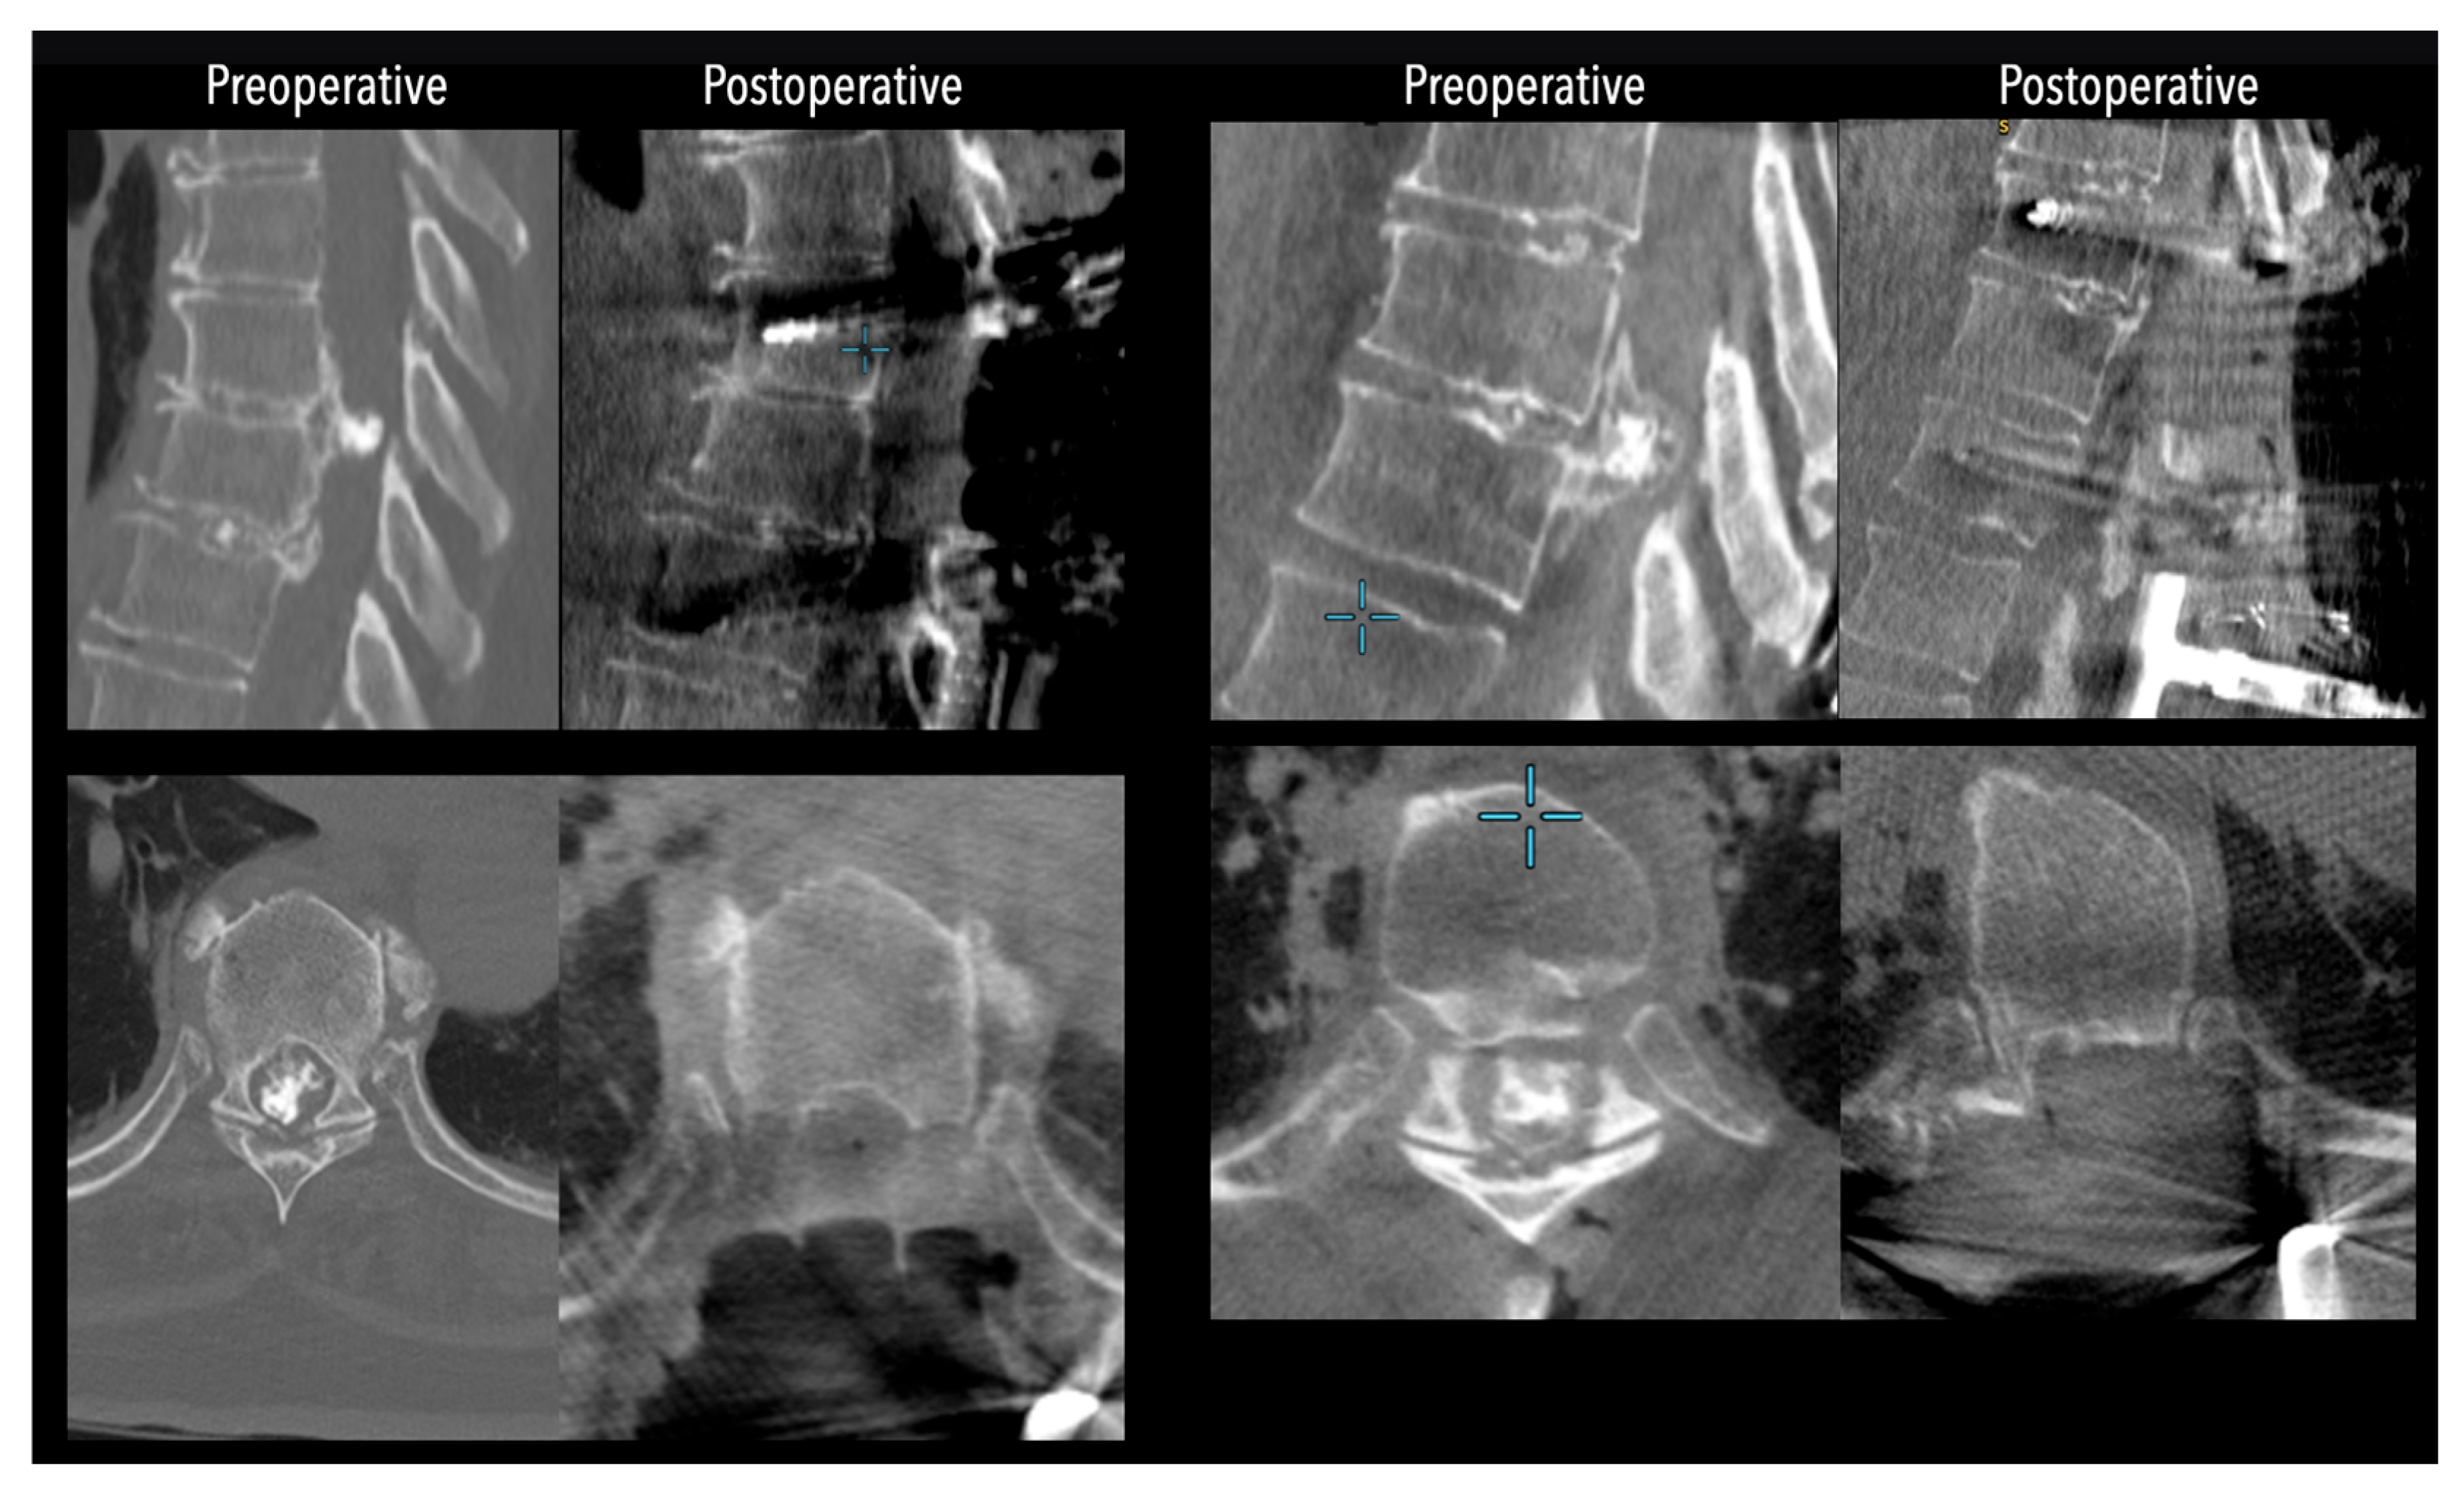

Figure 6. Left side: Comparative pre- and postoperative CT scan of a patient (axial views), illustrating complete discectomy.

In three of the seven cases, the exiting nerve root at the level of the herniation was ligated due to poor visualization and transected extradurally to improve access. In the remaining four patients, the nerve root was either preserved or dissected intradurally using isocool bipolar diathermy and microsurgical scissors. With gentle medial retraction of the cord under gravity and protection using a micro-patty, the calcified disc was exposed. The ventral dura, when intact, was incised sharply and dissected from the disc surface where possible (Figure 2a,b and Figure 3). Disc removal was performed using a hockey-stick-shaped Misonix bone scalpel with constant irrigation, guided by intraoperative neuronavigation. The disc material was resected to a depth of 1–2 mm beyond the posterior vertebral wall to ensure adequate decompression. A second O-Arm spin was routinely performed following discectomy to confirm satisfactory decompression, especially given the limitations of the postoperative MRI due to the metal artefact (Figure 4, Figure 5 and Figure 6).